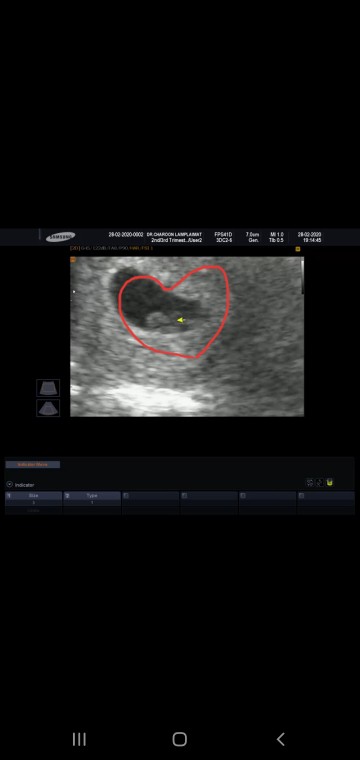

7w2d ค่ะ